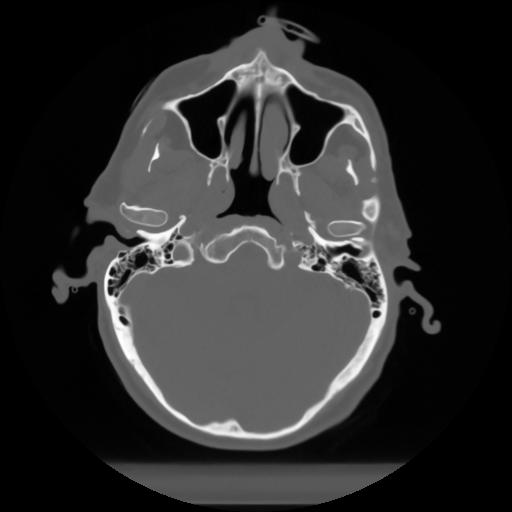

10 P.BLANDAS,,Axial,2.0,P.BLANDAS,,